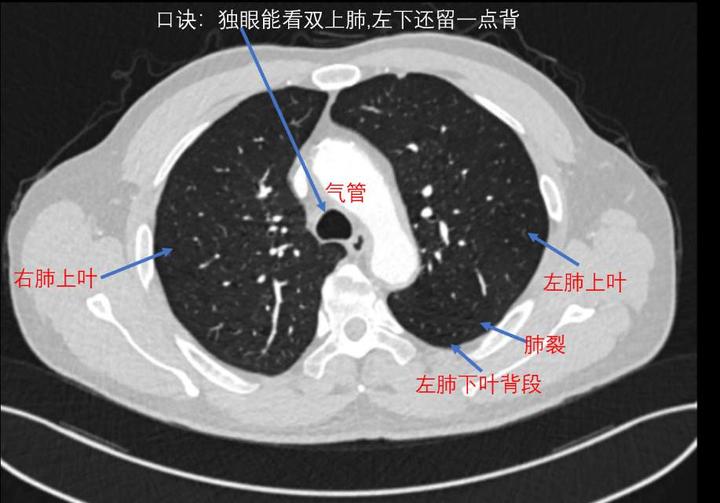

看见左右主支气管(双眼)层面:右肺上叶前段和右肺下叶背段,左肺上叶和

图片尺寸720x503